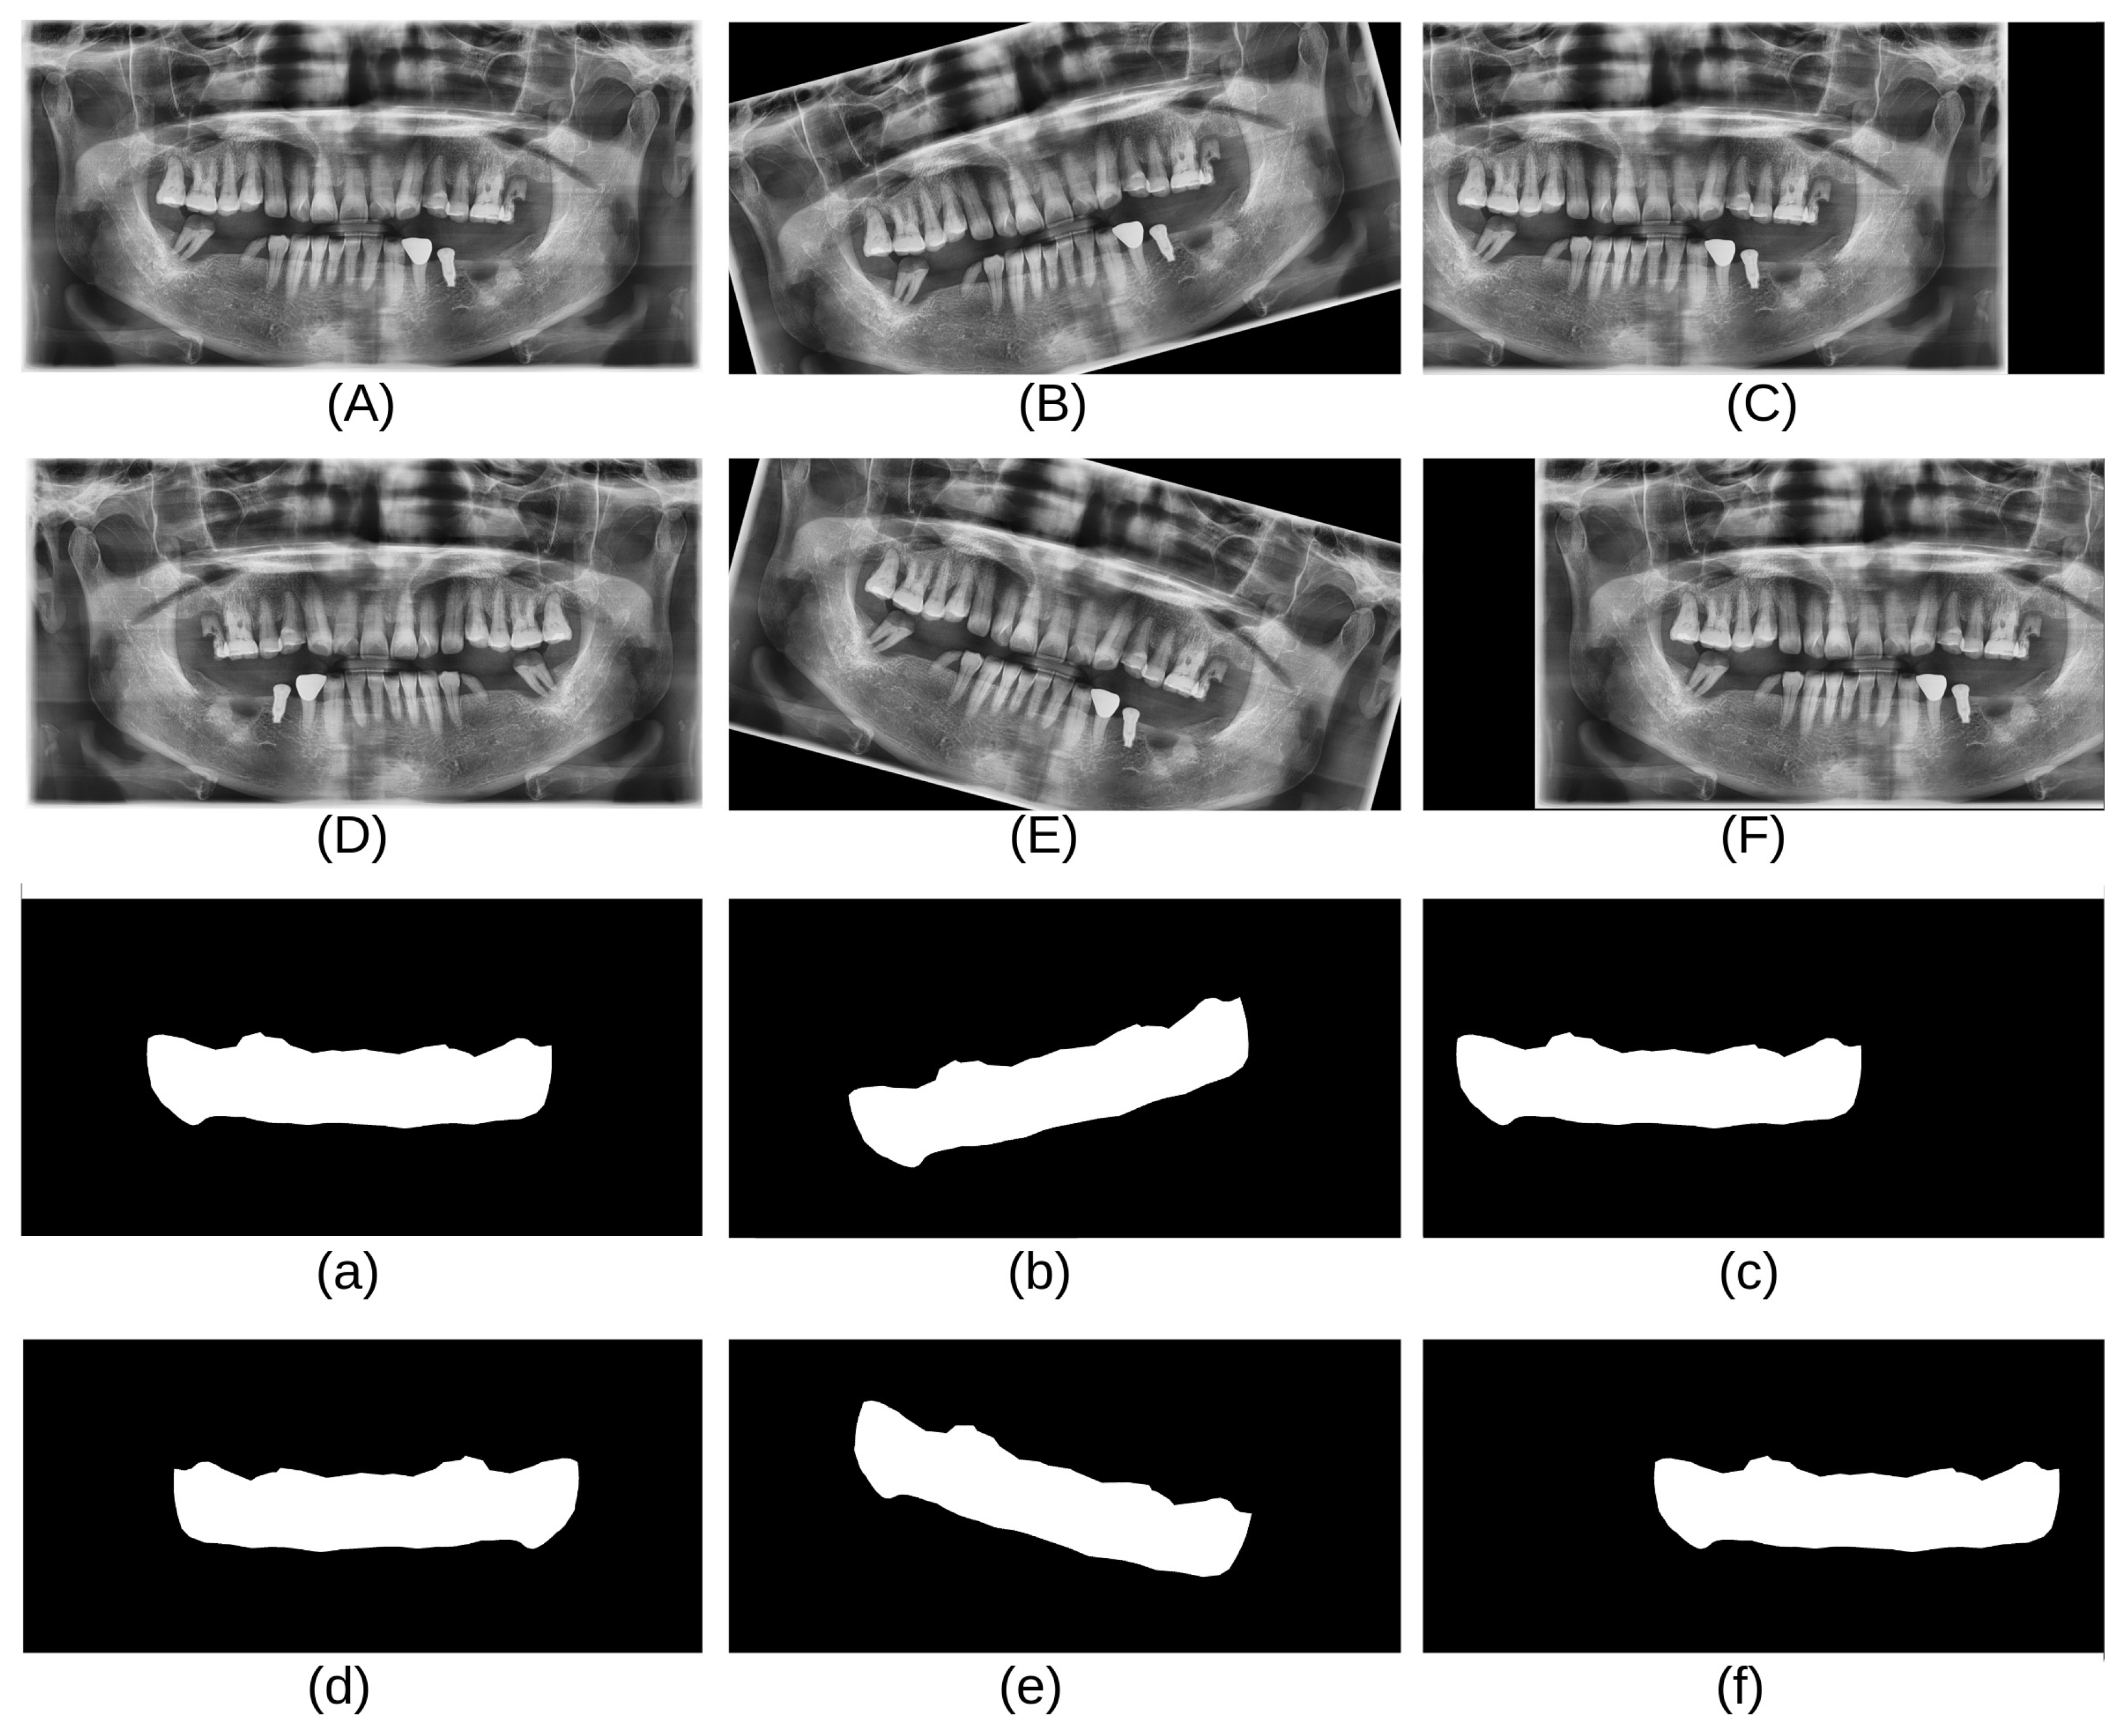

As shown in Table 1, the CBNUH dataset has a limited number of images, which can result in a low model accuracy. To address this, several data augmentation techniques, such as horizontal flips, rotations (15 degrees, −15 degrees), and shifting, were applied to increase the size of the dataset. These techniques help improve the orientation robustness of the model and prevent overfitting [13]. In this study, data augmentation techniques were applied to the CBNUH dataset, resulting in a fivefold increase in the original image count. Consequently, the dataset expanded to a total of 600 images, comprising both the augmented and original images. Figure 3 shows examples of the data obtained after applying each augmentation technique.

Figure 3. Images and masks after data augmentation techniques were applied: (A) original, (B) 15-degree rotation, (C) left shift, (D) horizontal flip, (E) −15-degree rotation, and (F) right shift. Each mask (af) aligns with its respective augmented image (AF).